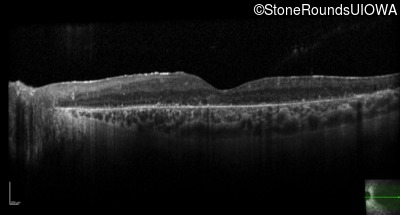

Optical Coherence Tomography - Left - 20/40 -1

Exemplar / OCT Stack

OCT Stack